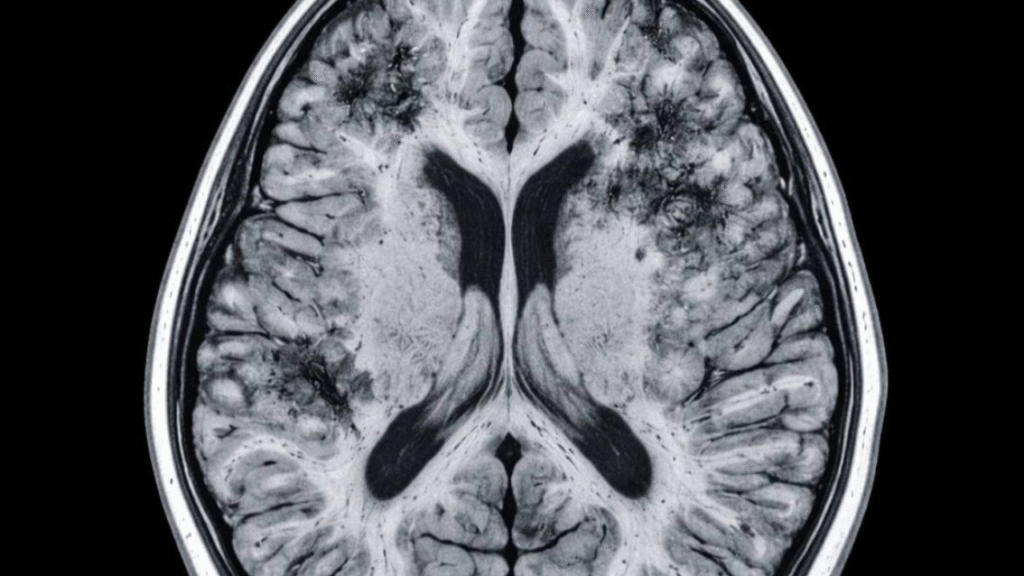

SAÚDE | Mais de 55 milhões de pessoas no mundo vivem com algum tipo de demência, segundo estimativas da Organização Mundial da Saúde (OMS). Uma pesquisa conduzida na Universidade de Harvard pelo neurologista Rudolph E. Tanzi, codiretor do Centro Henry e Allison McCance para Saúde Cerebral do Hospital Geral de Massachusetts, investiga genes ligados à doença de Alzheimer e criou estratégias para manter o cérebro ativo e saudável.